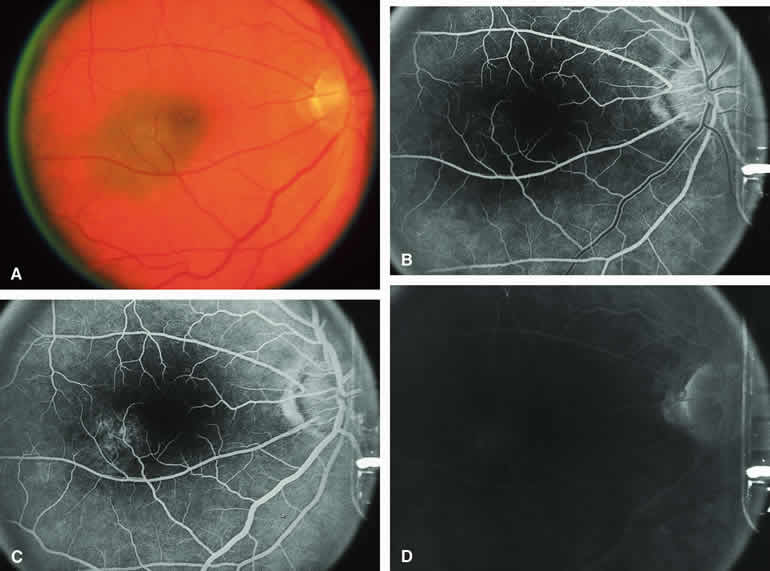

Typical Melanotic Choroidal Nevus

Fluorescein angiography of a typical choroidal nevus with bland surface features (see Fig. 1) shows the entire lesion to be hypofluorescent relative to the adjacent uninvolved choroid throughout the study. No large-caliber choroidal blood vessels are usually identifiable within the lesion. The retinal vasculature overlying the lesion appears well defined and normal on fluorescein angiography.